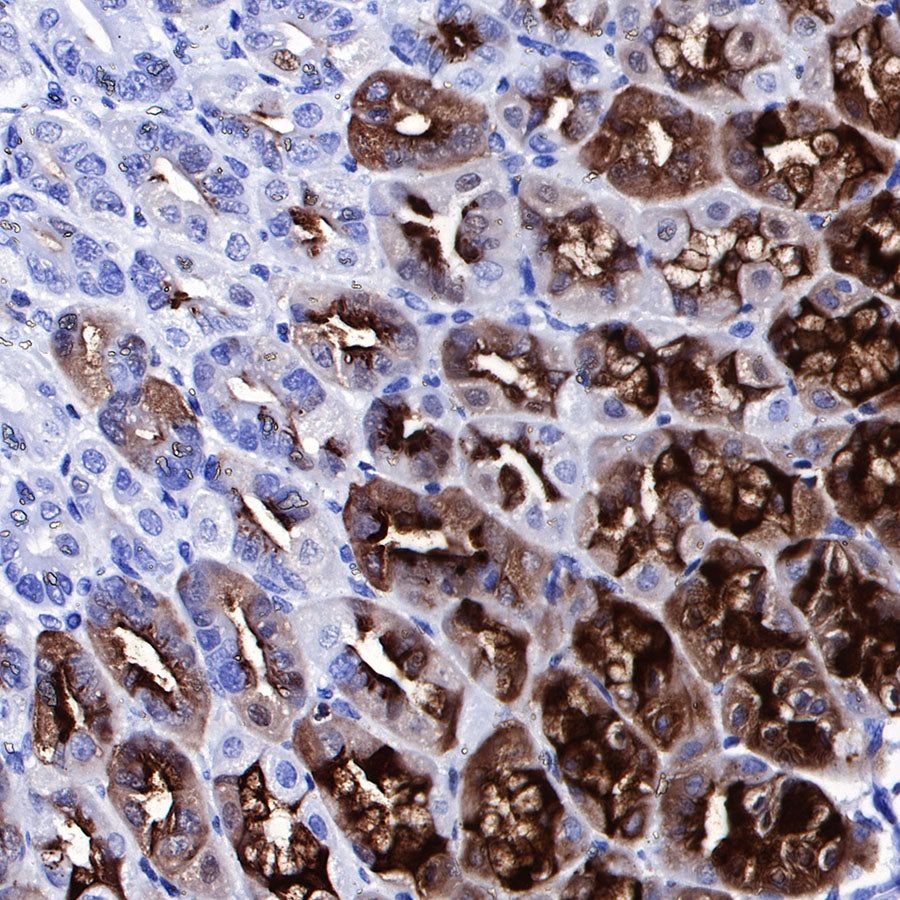

IHC shows positive staining in paraffin-embedded human stomach. Anti-PG II/PGC antibody was used at 1/1000 dilution, followed by a HRP Polymer for Mouse & Rabbit IgG (ready to use). Counterstained with hematoxylin. Heat mediated antigen retrieval with Tris/EDTA buffer pH9.0 was performed before commencing with IHC staining protocol.

Negative control: IHC shows negative staining in paraffin-embedded human liver. Anti-PG II/PGC antibody was used at 1/1000 dilution, followed by a HRP Polymer for Mouse & Rabbit IgG (ready to use). Counterstained with hematoxylin. Heat mediated antigen retrieval with Tris/EDTA buffer pH9.0 was performed before commencing with IHC staining protocol.